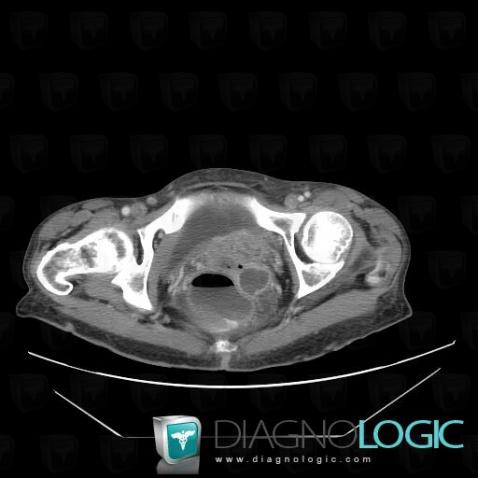

Voici les informations spécifiques à l'image clé ci dessus:

- Diagnostic Métastase, Localisation(s) Pelvis / Périnée, comportant les gammes Masse pelvienne kystique